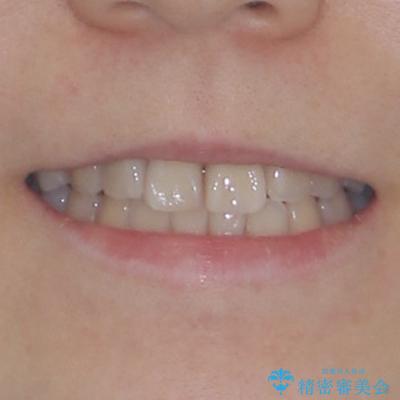

治療後

• 虫歯治療ついでに歯並びの後戻りを改善 インビザラインによる矯正治療 治療後画像